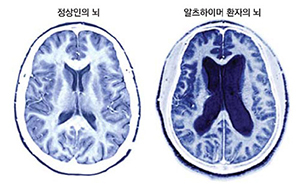

치매 환자가 체중이 급격히 줄어들 경우 사망 위험이 크게 증가한다는 연구 결과가 나왔다.